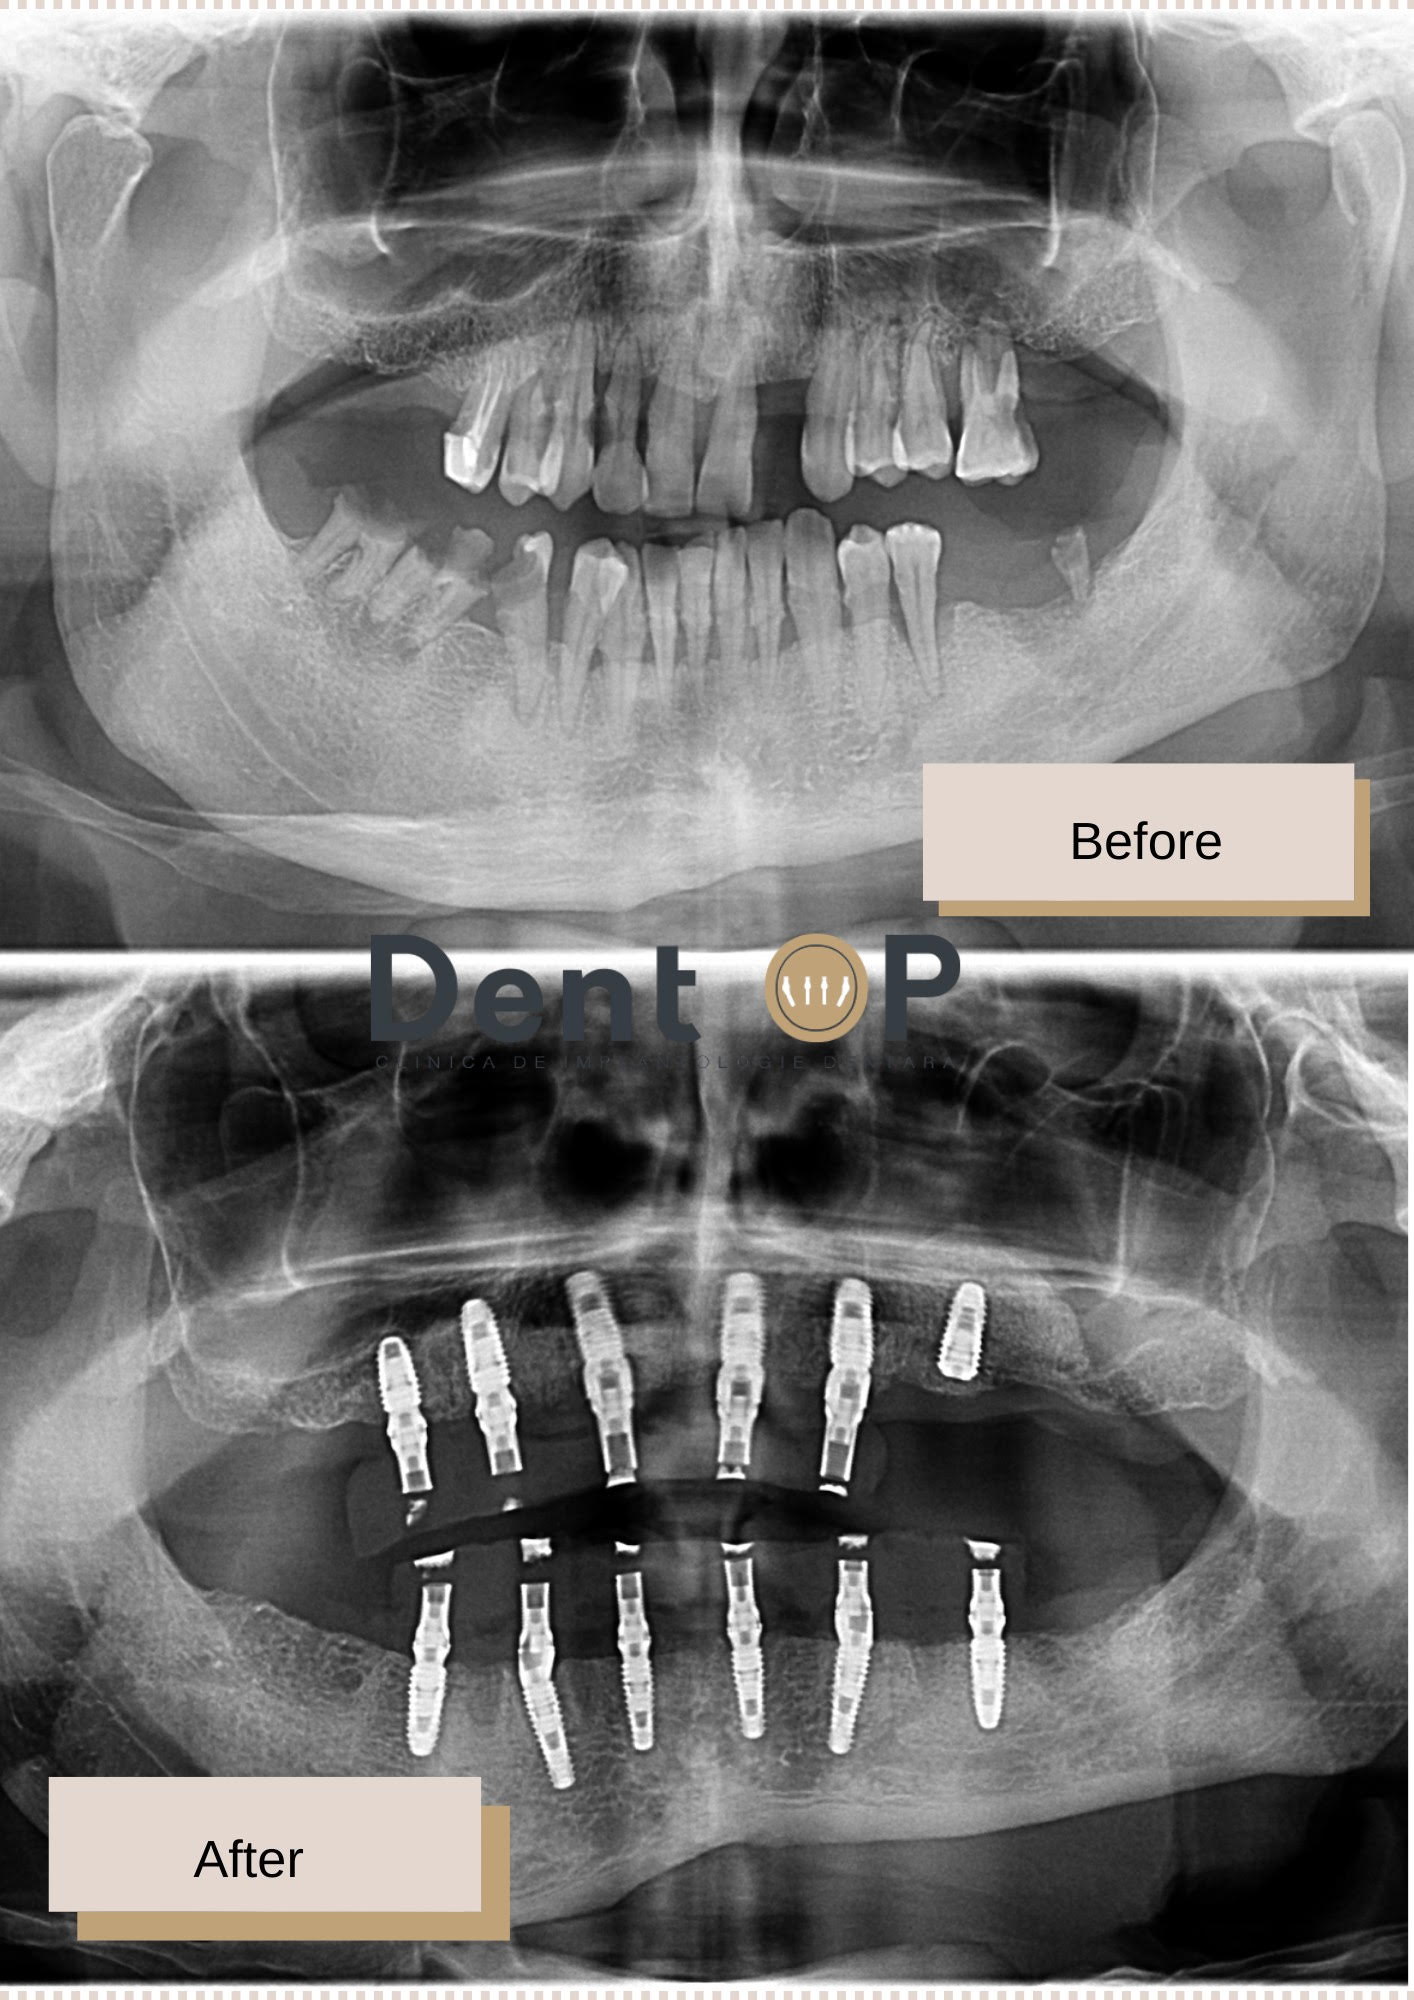

I s-au extras toți cei 23 de dinți din cauza bolii parodontale agresive. Iată cum arată acum zâmbetul său

Domnul A. este unul dintre pacientii la care boala parodontala a avansat considerabil, astfel a necesitat extragerea danturii sale și înlocuirea acesteia cu implanturi dentare.

În cadrul intervenției, i-au fost inserate 12 implanturi dentare cu ajutorul procedurii de Sedare Conștientă, iar după 24h, pacientul primise deja un set nou de dinți ficși sub forma unei danturi provizorii care să-l ajute timp de 4-6 luni. După acest timp în care gingia s-a vindecat complet, iar implanturile s-au vindecat a urmat etapa inserării lucrărilor finale. Dantura a fost aleasă cu atenție pentru a i se potrivi pacientului, iar cu acordul său a fost aleasă culoarea, forma și mărimea potrivită a dinților.